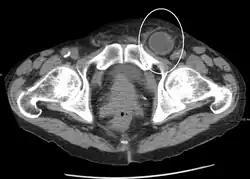

Medical imaging

A physician may diagnose an inguinal hernia, as well as the type, from medical history and physical examination.[11] For confirmation or in uncertain cases, medical ultrasonography is the first choice of imaging, because it can both detect the hernia and evaluate its changes with for example pressure, standing and Valsalva maneuver.[12]

When assessed by ultrasound or cross sectional imaging with CT or MRI, the major differential in diagnosing indirect inguinal hernias is differentiation from spermatic cord lipomas, as both can contain only fat and extend along the inguinal canal into the scrotum.[13]

On axial CT, lipomas originate inferior or lateral to the cord, and are located inside the cremaster muscle, while inguinal hernias lie anteromedial to the cord and are not intramuscular. Large lipomas may appear nearly indistinguishable as the fat engulfs anatomic boundaries, but they do not change position with coughing or straining.[13]

An incarcerated inguinal hernia as seen on cross sectional CT scan -